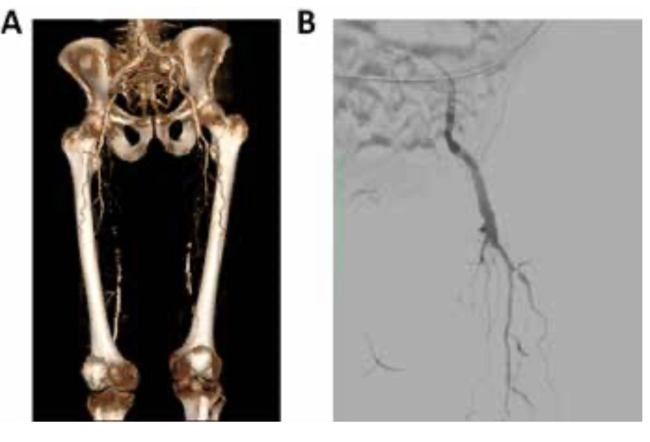

MSCT of the lower limb arteries with intravenous contrast was performed, which allowed a diagnois of bilateral SFA occlusion and left-sided popliteal artery occlusion (PoA) (Figure 1A).

The right brachial artery was punctured retrogradely under local anaesthesia. A 6F introducer was inserted and 5000 U systemic heparinization was performed. Then, a diagnostic catheter was inserted into the left CFA via a guidewire. Angiography found extended total-length SFA occlusion from the ostium, without a stump, and PoA occlusion to the knee joint cleft (Figure 1B).